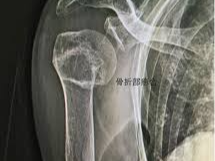

상완골 골절의 부위별 구분

• 상부 골절 (상완골 근위부 골절): 어깨에 가까운 부위

• 중간부 골절 (상완골 간부 골절): 팔 중심 부위

• 하부 골절 (상완골 원위부 골절): 팔꿈치 근처